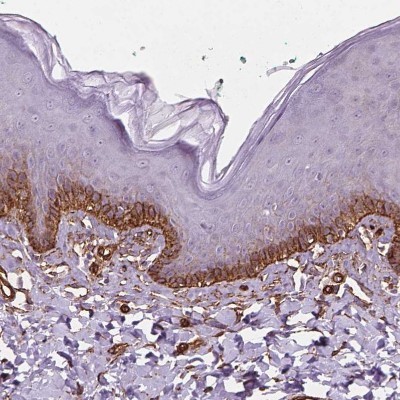

- Immunohistochemistry-Paraffin: EGFL8 Antibody [NBP2-49327] - Staining of human skin shows strong membranous positivity in squamous epithelial cells.